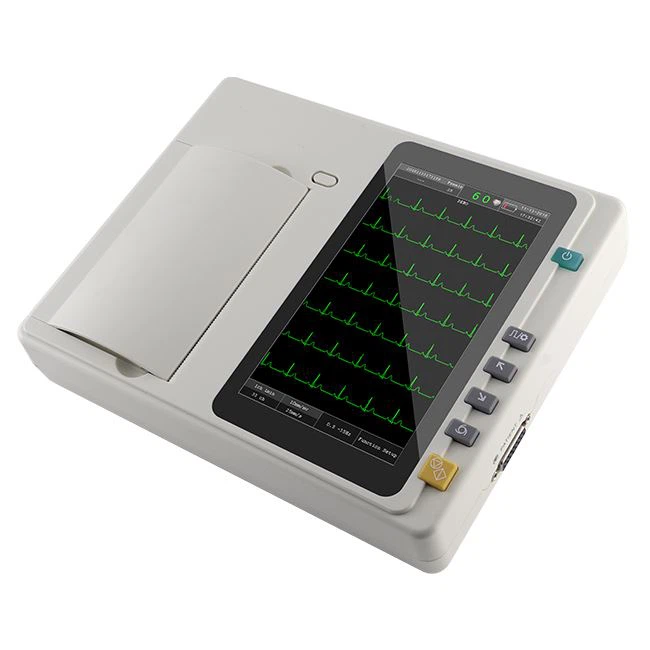

Bionet CardioTouch 3000 12 Channel ECG Machine

Bionet CardioTouch 3000 12 Channel ECG Machine

.jpeg) ECG 12 CHANNEL - MEDEXBIO

ECG 12 CHANNEL - MEDEXBIO

ECG MACHINE 6 CHANNEL - MEDEXBIO

ECG MACHINE 6 CHANNEL - MEDEXBIO

Digital 6 Channel ECG Machine

Digital 6 Channel ECG Machine